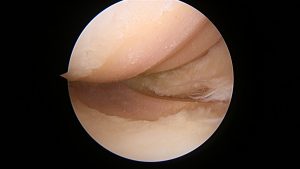

後十字靭帯再建術

先日、東京女子医科大学整形外科教授の岡崎賢先生を招いて

後十字靭帯(PCL)再建手術を行いました。

私は、ほとんどの膝の手術を一人で行っていますが、

この手術だけは、一人で行うことは難しいと考えています。

できなくはなくても、手術時間が長くなりすぎると術後の腫れや痛みが強くなり、

患者さんに負担をかけてしまいます。

関節鏡手術を完全にこなせる医師二人がかりで行うことで、安全確実に、短時間で

手術を終えることができます。